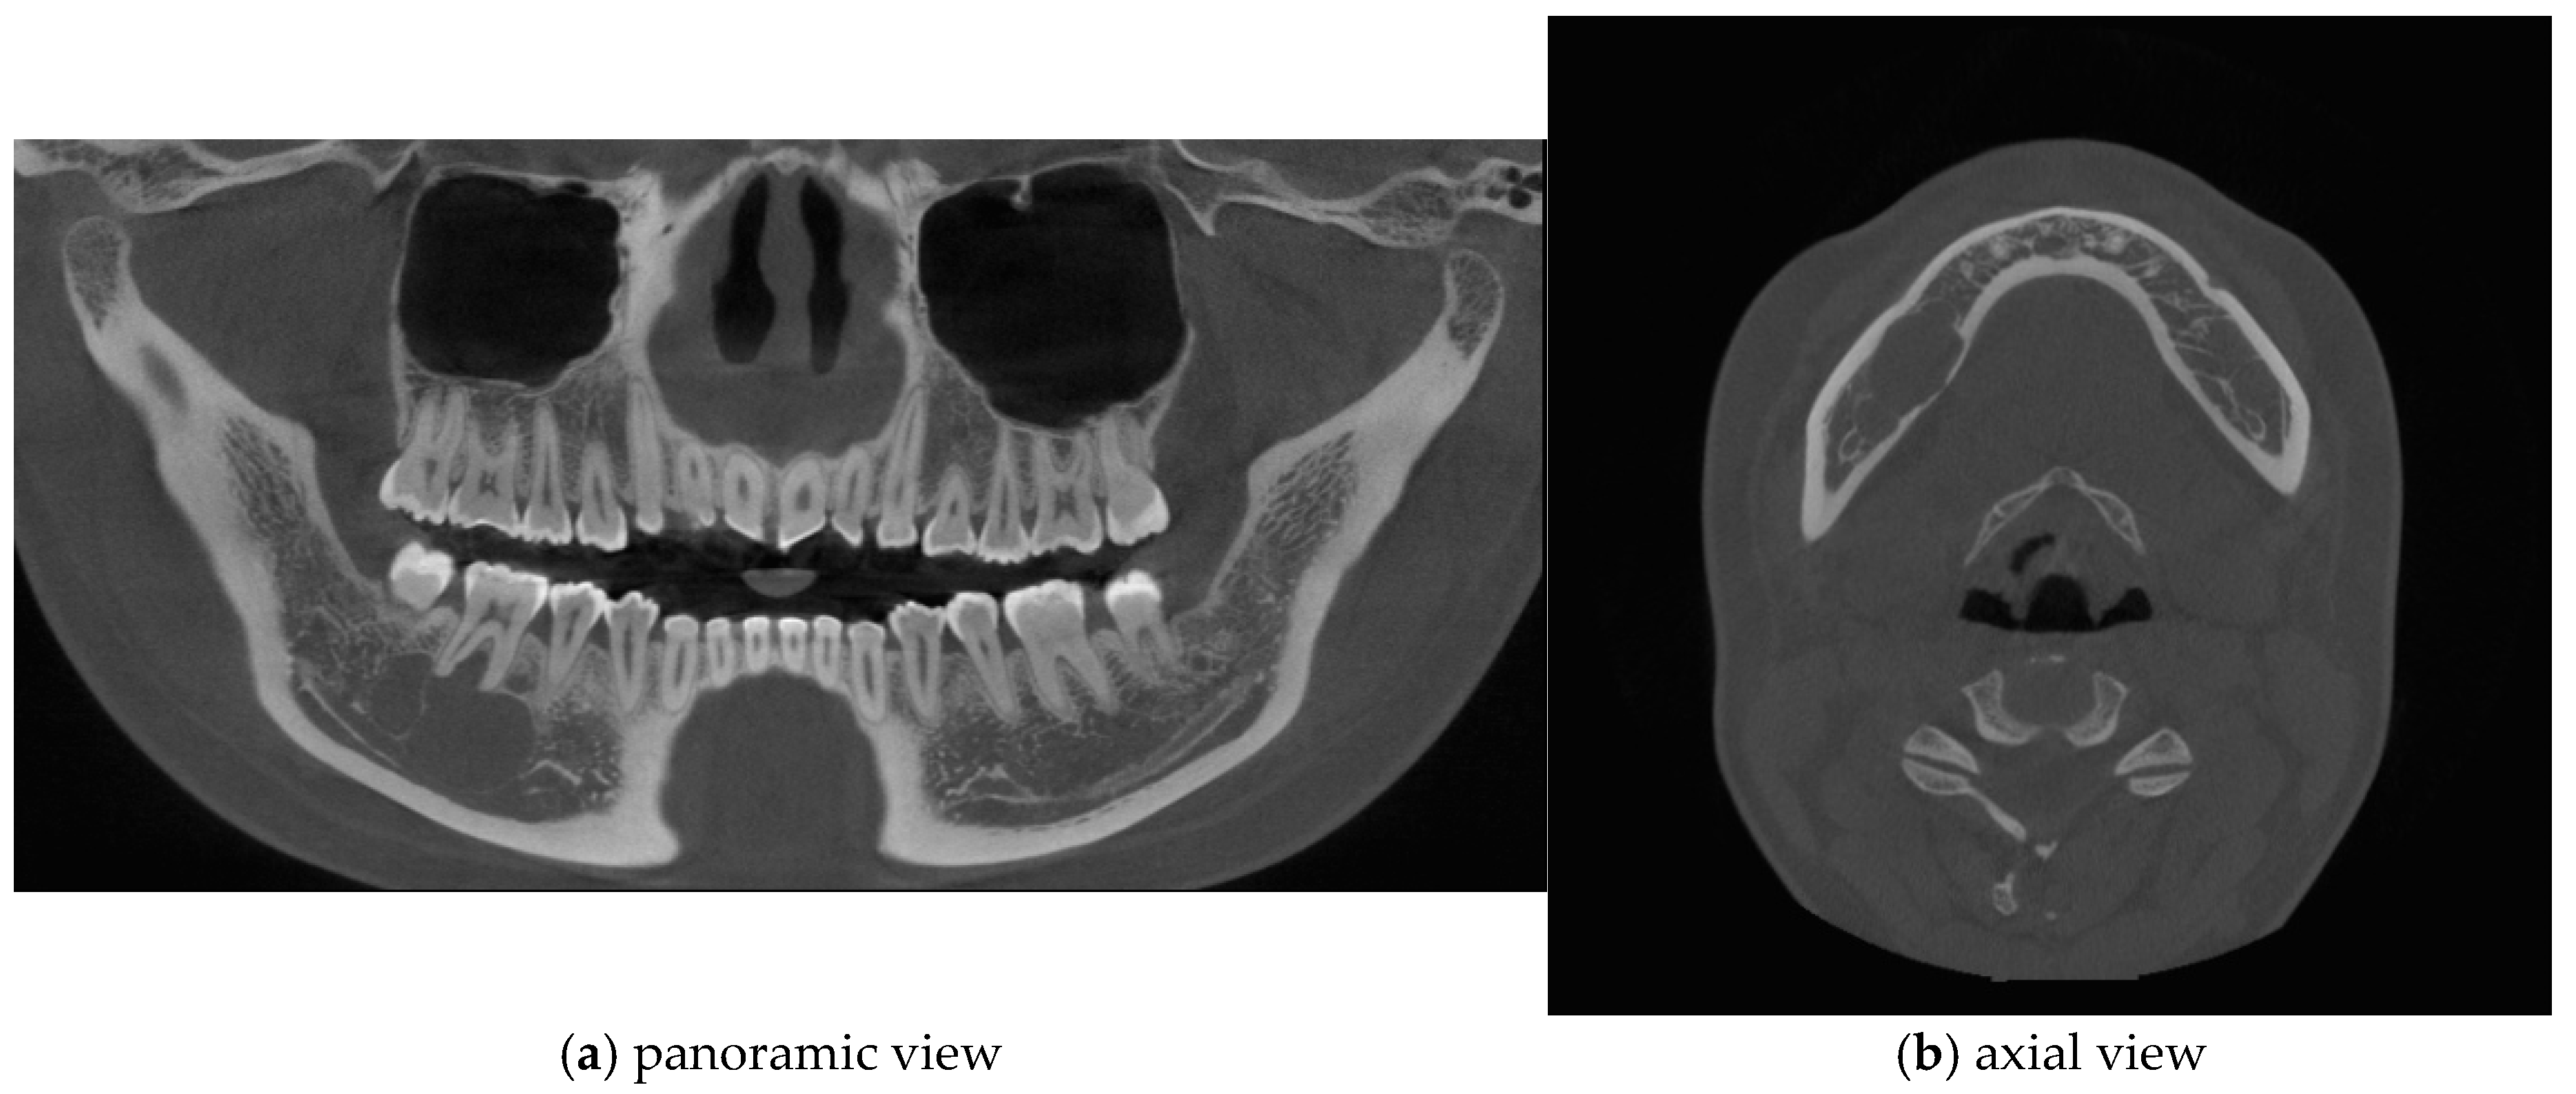

Figure 2.

Cone-beam computed tomography (CBCT) imaging revealed thinning of the lingual cortical bone in the region of the right mandibular second premolar and first molar, as well as inferior displacement of the right mandibular canal.